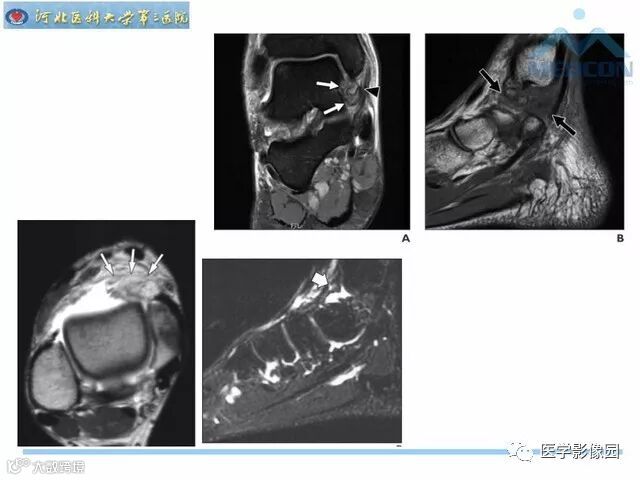

踝关节撞击综合征影像诊断,干货满满,值得收藏!

导读:踝关节撞击综合征影像诊断。干货满满,值得收藏!

踝关节撞击综合征影像诊断。干货满满,值得收藏!